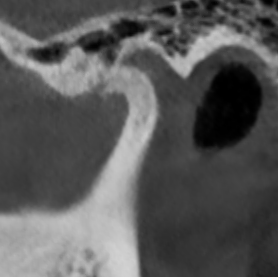

Перед началом лечения я провожу часовую первичную консультацию. Для этой встречи вам необходимо сделать «МРТ ВНЧС» и «КЛКТ двух челюстей с захватом ВНЧС в привычном прикусе».

Во время консультации мы смотрим и анализируем ваши исследования. Я подробно объясняю строение ВНЧС, показываю все причинные факторы вашей проблемы, отвечаю на все вопросы «Почему?»